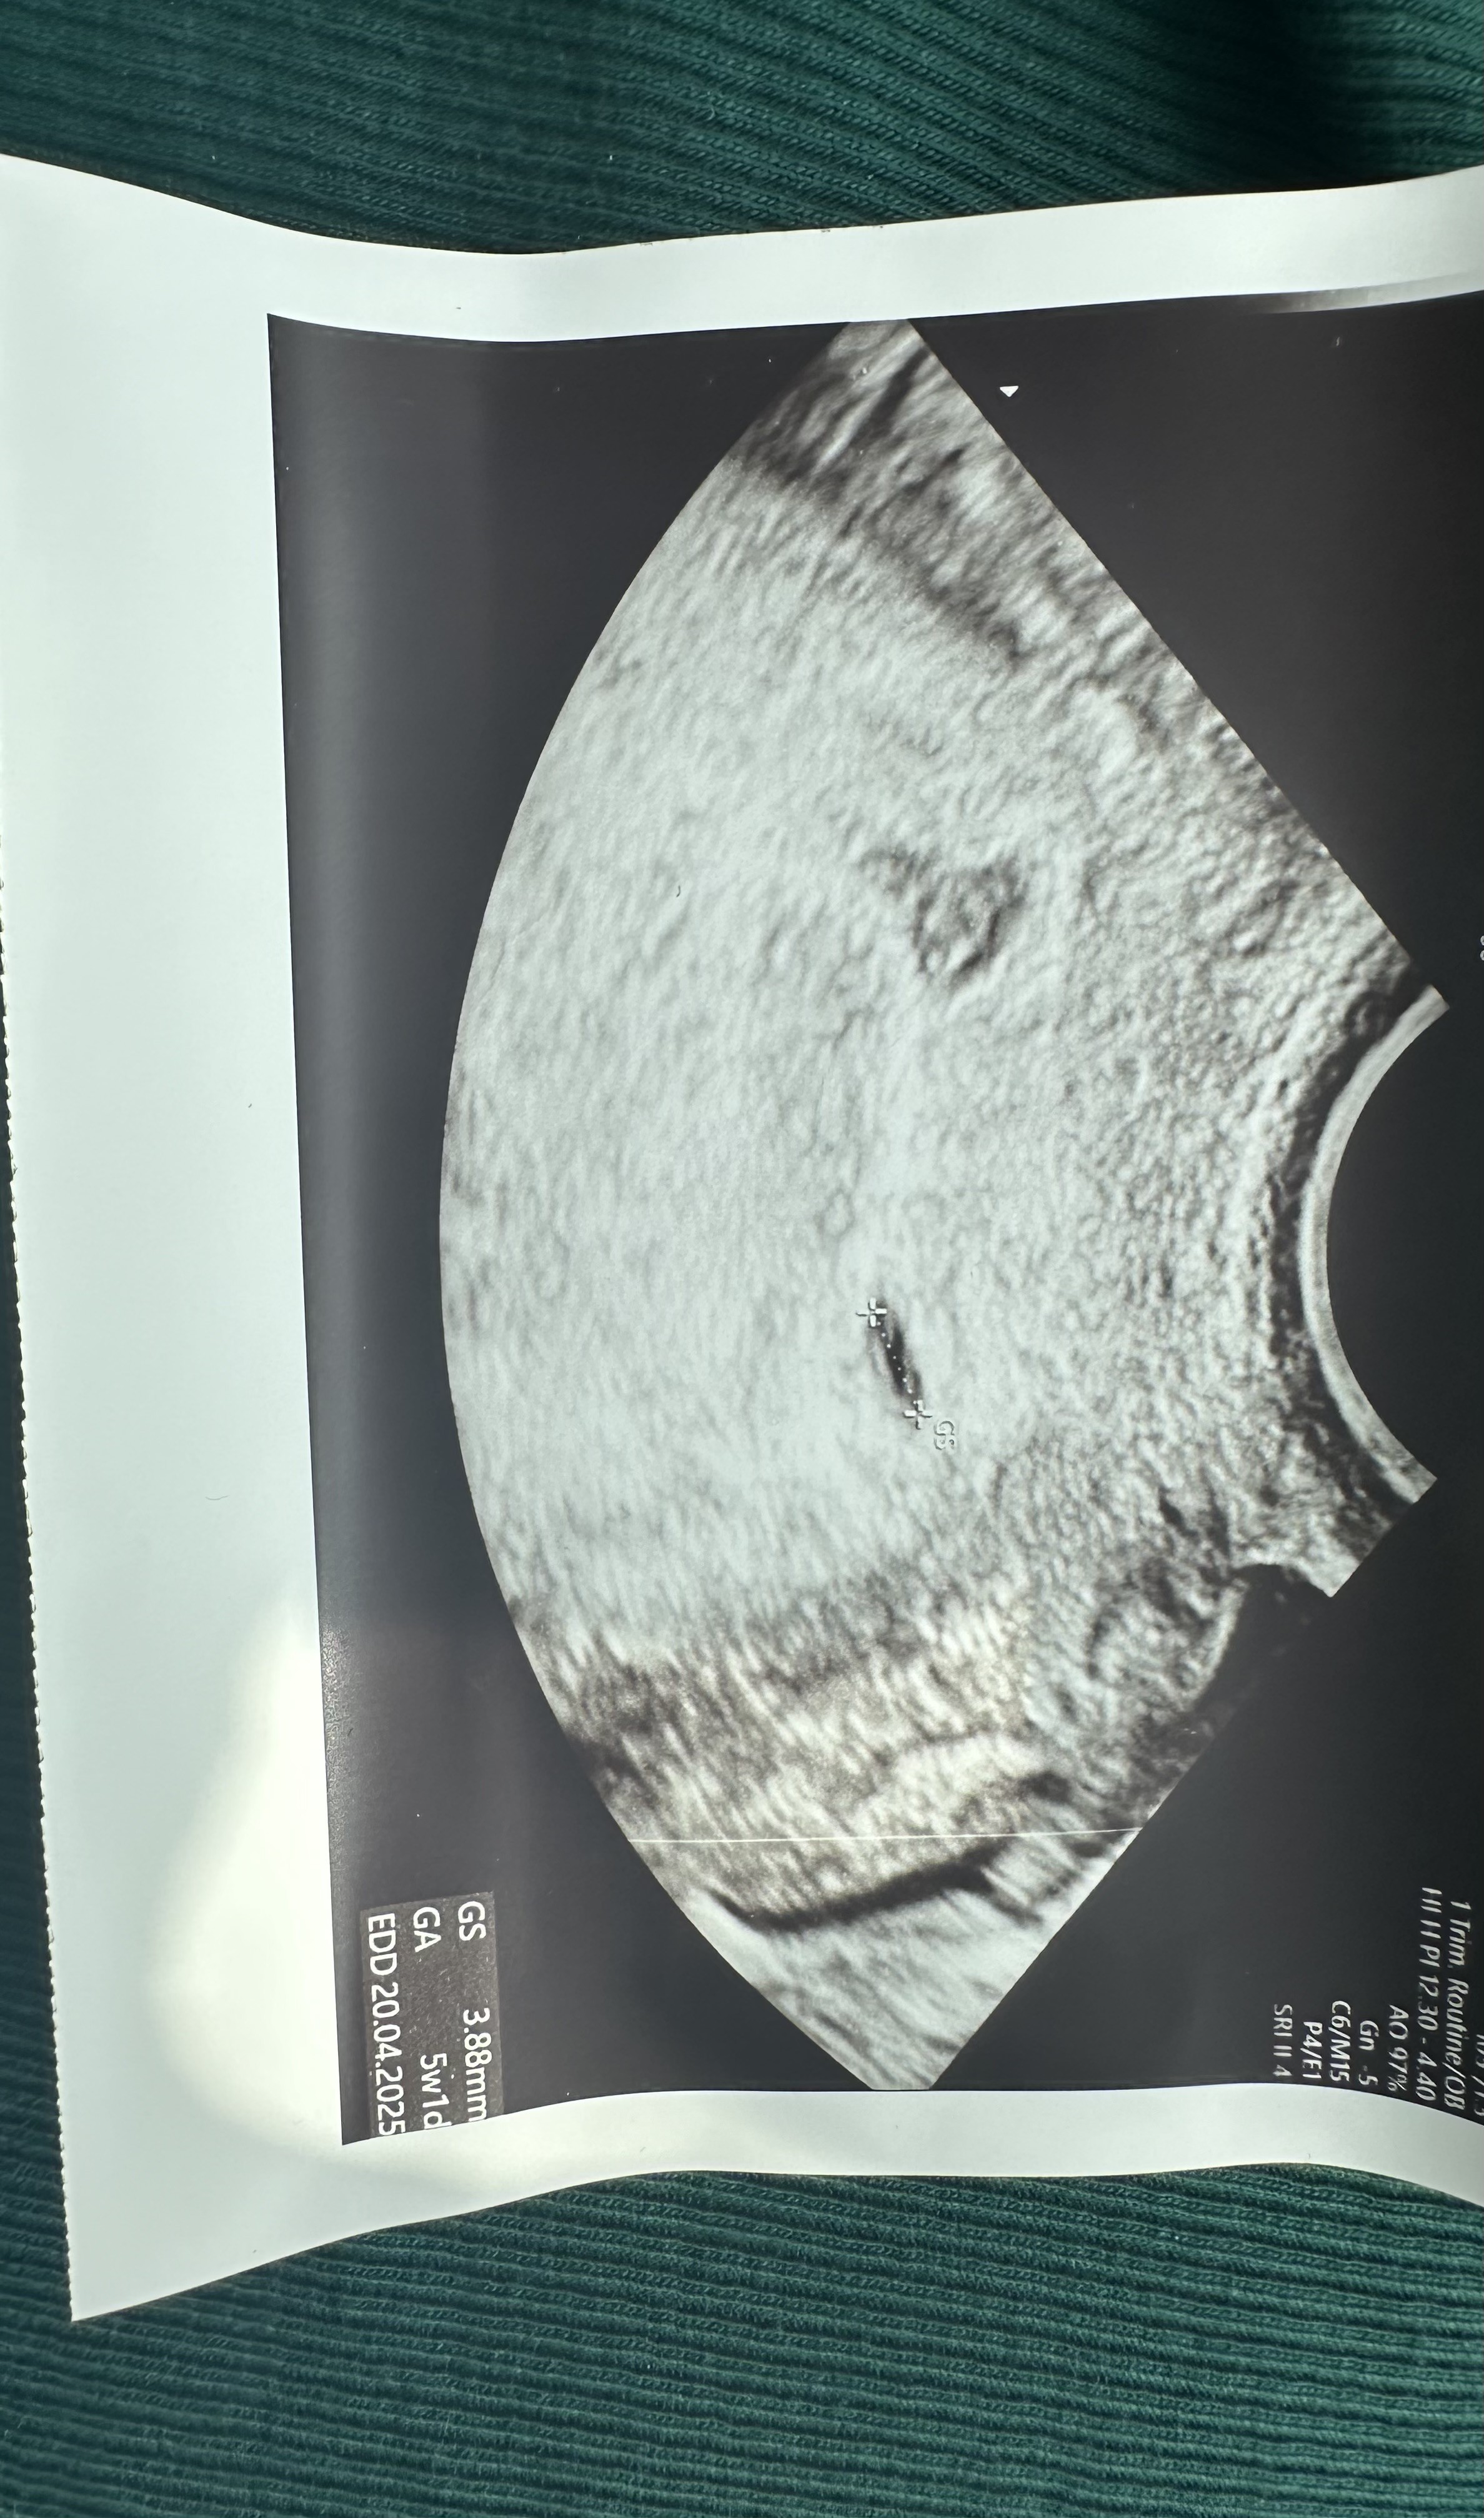

Ja już po pierwszej wizycie 🙈 bardzo szybko bo musiałam niestety pójść po L4 więc zarodka jeszcze nie ma ale pęcherzyk obecny ♥️

To moja pierwsza ciąża i tyle obaw w głowie, że szok 🥹 ale narazie ulga, że chociaż pęcherzyk jest tam gdzie powinien 🤩 za 3 tygodnie kolejna wizyta więc mam nadzieję, że serduszko już będzie 🥰

Załączniki

• IMG_2451.jpeg

IMG_2451.jpeg

1,2 MB · Wyświetleń: 81